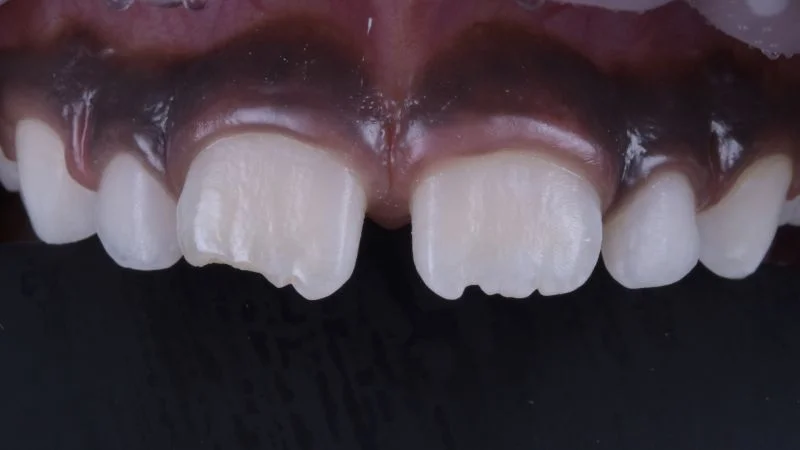

Behandlungsergebnis.

Ansicht des Zahnes 11 von lateral.

Restauration nach Fertigstellung.

Polierte Oberfläche der Restauration an Zahn 11. 3M Sof-Lex Ausarbeitungs- und Polierscheiben Medium, Fein, Superfein, Bimssteinpaste und Polierpaste kamen zum Einsatz. Die Ausformung der Inzisalkante erfolgte mit feinkörnigen rotierenden Instrumenten.